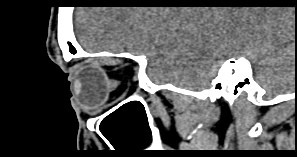

Орбиты (или глазницы) – это костные углубления в лицевом черепе, где расположены глазные яблоки, окруженные жировой клетчаткой, а также слезные железы, слезные каналы, сосуды, нервы, мышцы и связки глаза. Такая небольшая по объему область содержит важные анатомические структуры, обеспечивающие нормальную функцию органа зрения.

Кроме того, область орбиты тесно связана с близлежащими структурами – полостью черепа с расположенным в ней головным мозгом, а также с полостью носа, околоносовыми пазухами и носоглоткой. Различные патологические процессы могут развиваться как в самой глазнице, так и в околоорбитальных структурах, но при этом распространяться на область орбит.

Сложное строение глазницы и взаимосвязь с соседними анатомическими структурами затрудняет диагностику заболеваний глазного яблока и его придатков. Одним из наиболее информативных методов обследования органа зрения и окружающих тканей является мультиспиральная компьютерная томография. Кроме высокой информативности методика отличается быстротой и неинвазивностью (то есть не требует вмешательства в организм человека). Принцип получения изображений построен на применении ионизирующего излучения и разной способности тканей поглощать рентгеновские лучи.

Новейшее оборудование наших медицинских центров представлено современными мультиспиральными компьютерными томографами экспертного класса TOSHIBA AQUILION. Различные версии аппаратов способны выполнять одновременно 64 или 128 тончайших срезов исследуемой зоны. Таким образом получаются детальные изображения высокого качества за несколько секунд. Толщина срезов при этом составляет от 0,5 мм, что позволяет выявить патологические процессы на самых ранних стадиях развития, тем самым повысить шансы больного на успешное лечение.

На основе результатов сканирования аппараты выстраивают трехмерные модели органов и тканей, что дает возможность увидеть их точное пространственное расположение по отношению друг к другу.

Мультиспиральная компьютерная томография лучше всего визуализирует ткани с высокой плотностью, к которым, в частности, относится костная ткань. Это делает КТ незаменимой при диагностике травматических повреждений глазниц, а также для выявления инородных тел орбит.

По результатам КТ орбиты глаза врач может оценить состояние:

- костных стенок глазницы, верхней и нижней глазничных щелей;

- глазных яблок

- стекловидного тела;

- мышц глаза: нижней, верхней, косой, прямых мышц (латеральной и медиальной);

- глазничной артерии и вены;

- зрительных нервов;

- слезных желез;

- ретробульбарной (расположенной позади глазного яблока) клетчатки.